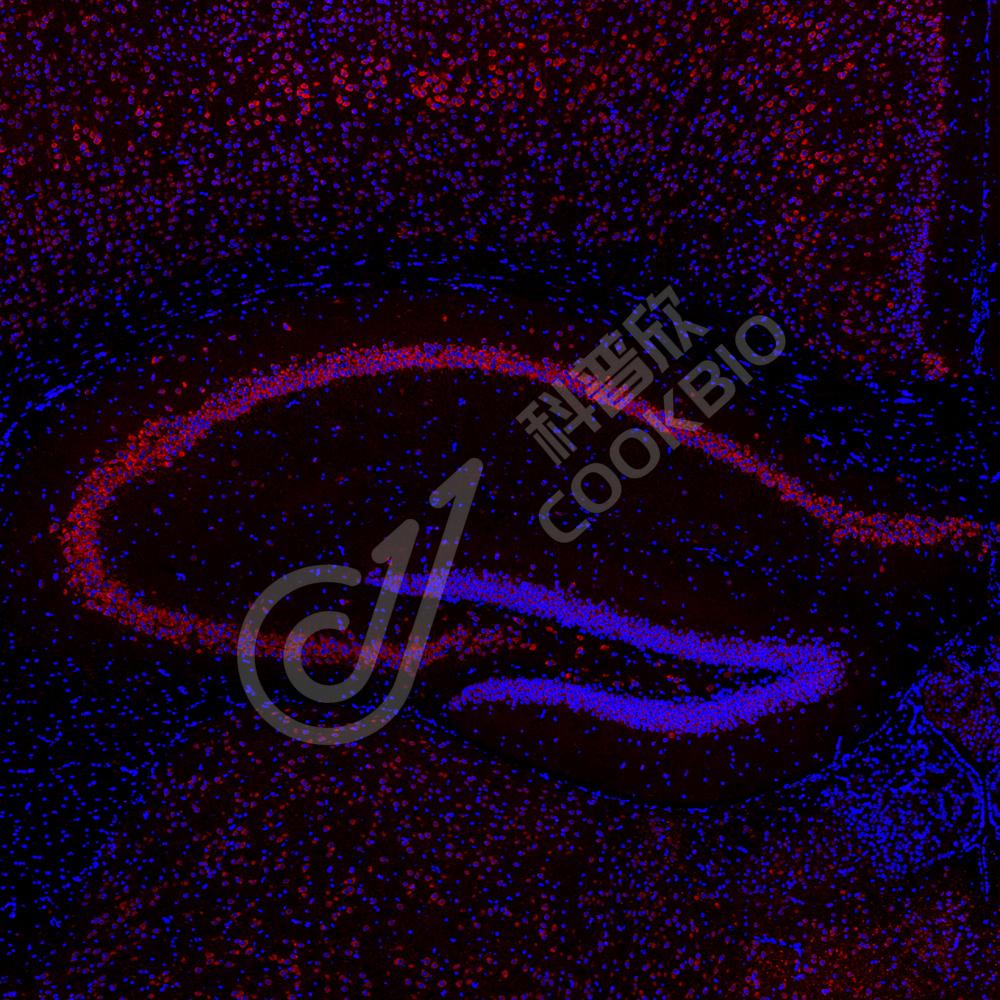

图像

IHC检测Eph receptor B4/HTK蛋白(货号 K1334086).

样品: 人结肠, 4%多聚甲醛 (货号KSG1101) 固定12-24小时.

抗原修复: 柠檬酸抗原修复液(干粉, pH 6.0) (KSG1201), 98℃, 20分钟.

—抗: 1: 2000稀释, 4℃ 孵育过夜.

二抗: S-vision免疫组化多聚二抗(山羊抗兔),即用型 (货号KB3906), 室温孵育20分钟.

样品: 人肝, 4%多聚甲醛 (货号KSG1101) 固定12-24小时.